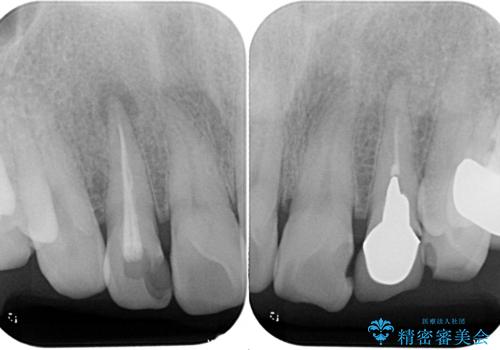

- 前歯の色味が気になるとのことで来院された患者様です。左上の2番目の歯の歯茎のラインと被せものの境目の適合が悪い状態だったのでオールセラミッククラウンによる補綴治療を行っていくことになりました。

金属の土台を外し、ファイバーコアを築造し、オールセラミッククラウンに適切な形に整えました。

左上の2番目の歯の型どりの段階で患者様より右上の2番目の歯も治療をしてほしいとのことで、根管治療(保険診療)、ファイバーコア、オールセラミッククラウンによる補綴治療を行いました。